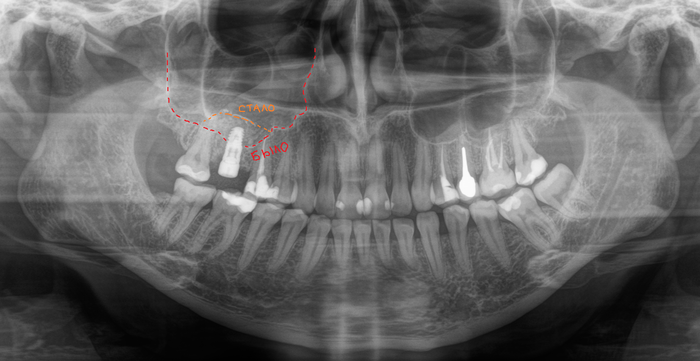

А теперь пример синус-лифтинга и имплантации, но через 2 месяца после того, как был удален 6-ой зуб на верхней челюсти. Этой пациентке удалили 6-ку около недели назад в другой клинике. Ассистентка сделала компьютерную томографию.

В связи с тем, что после удаления прошла всего неделя, то и на снимке мы видим «темную дыру», как ту, что оставила в твоем сердце бывшая. В том месте, где раньше был зуб. То есть костной ткани в этой области нет. К операции я приступил через 2 месяца. Повторную компьютерную томографию после заживления лунки делать не стали, но поверьте все зажило достаточно для того, чтобы можно было провести операцию. В ходе операции жесткой стабилизации имплантата добиться не удалось, поэтому я принял решение установить заглушку, а не формирователь десны. Почему? А потому, что если пациентка начнет грызть сухари, то на имплантат, в частности формирователь, может быть оказано сильное давление, в связи с чем имплантат может расшататься или «улететь» в пазуху. Заодно в утиль пошла и 8-ка.